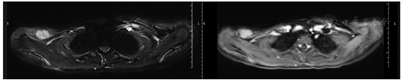

2018年6月,患者无意间触及原锁骨肩峰端手术断端肿物并进行性增大。患者回院复查行相关检查,考虑局部复发(图1)。于2018年6月15日至2019年3月20日行10个周期化疗,方案为VAC/IE方案。2019年4月12日在全身麻醉下行右锁骨残端骨肿瘤切除术,术中冰冻病理结果:上、下、内、外、基底切缘均为肌肉或纤维结缔组织,未见肿瘤。术后病理结果:(右锁骨肿物)纤维脂肪及横纹肌之间见数个小片状分布的肿瘤细胞巢,考虑尤文肉瘤复发。2019年5月8日至2019年8月20日行6个周期化疗,VAC/IE方案。化疗过程顺利。其后患者因故未返院复查。